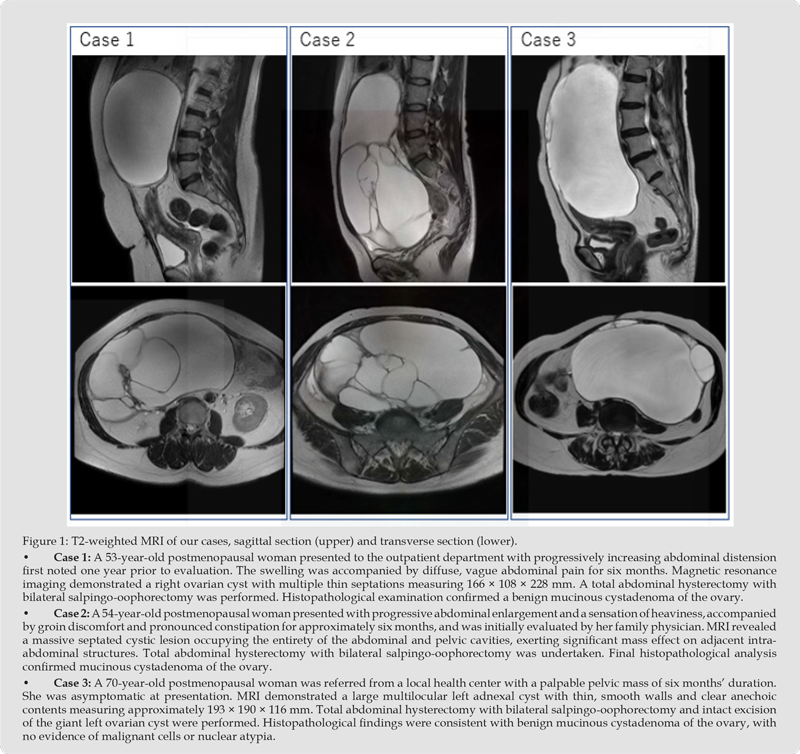

Giant ovarian tumors have become increasingly uncommon owing to the early detection of adnexal pathology facilitated by the widespread use of advanced imaging modalities in contemporary clinical practice [1,2]. In the literature, large or giant ovarian cysts are typically defined as lesions exceeding 20 cm in diameter or extending above the level of the umbilicus. Ovarian cystadenomas are frequently discovered incidentally, often in the absence of specific clinical manifestations, though complicated presentations may include abdominal pain. Among these, mucinous cystadenomas are more prevalent and possess the capacity to enlarge substantially while remaining undiagnosed until reaching considerable dimensions, commonly detected incidentally during routine physical examinations or radiologic imaging [3-5]. If left untreated, they may attain remarkable size and give rise to serious complications such as abdominal compartment syndrome [6] and cyst rupture [7], both of which necessitate urgent surgical intervention. The objective of this mini-review is to underscore such presentations in surgically high-risk postmenopausal women and to expand the existing literature pertaining to this age group, including our cases (see Figure 1).

In postmenopausal women or when malignancy is suspected, total hysterectomy with bilateral salpingo-oophorectomy is generally advocated. Although laparoscopy represents a first-line approach for many adnexal cysts, its applicability in the management of giant cysts remains limited. Technical constraints, particularly restricted operative space, render laparoscopic excision of extremely large ovarian cysts feasible only in highly selected cases and in the hands of experienced surgeons. Although cystadenomas are benign epithelial neoplasms, rare cases of coexistence with anaplastic carcinoma or malignant ovarian Brenner tumors have been reported [10]. According to available literature, mucinous tumors are typically unilateral, as observed in our cases (Figure 1), and are classified as benign (75%), borderline (15%), or malignant (10%). If untreated, these neoplasms may progress to invasive mucinous carcinoma [3-5,11]. Benign ovarian mucinous cystadenomas constitute the majority of mucinous tumors [3-5,11]. They are capable of attaining extraordinary dimensions and rank among the largest tumors recorded in the human body, as exemplified by our patients. In postmenopausal women, the incidence of borderline ovarian tumors declines significantly and is therefore relatively uncommon. Mucinous tumors most frequently arise during the fifth and sixth decades of life; however, their true incidence in postmenopausal women may be underestimated due to earlier detection. Our patients were 53, 54, and 70 years of age and postmenopausal at the time of diagnosis.